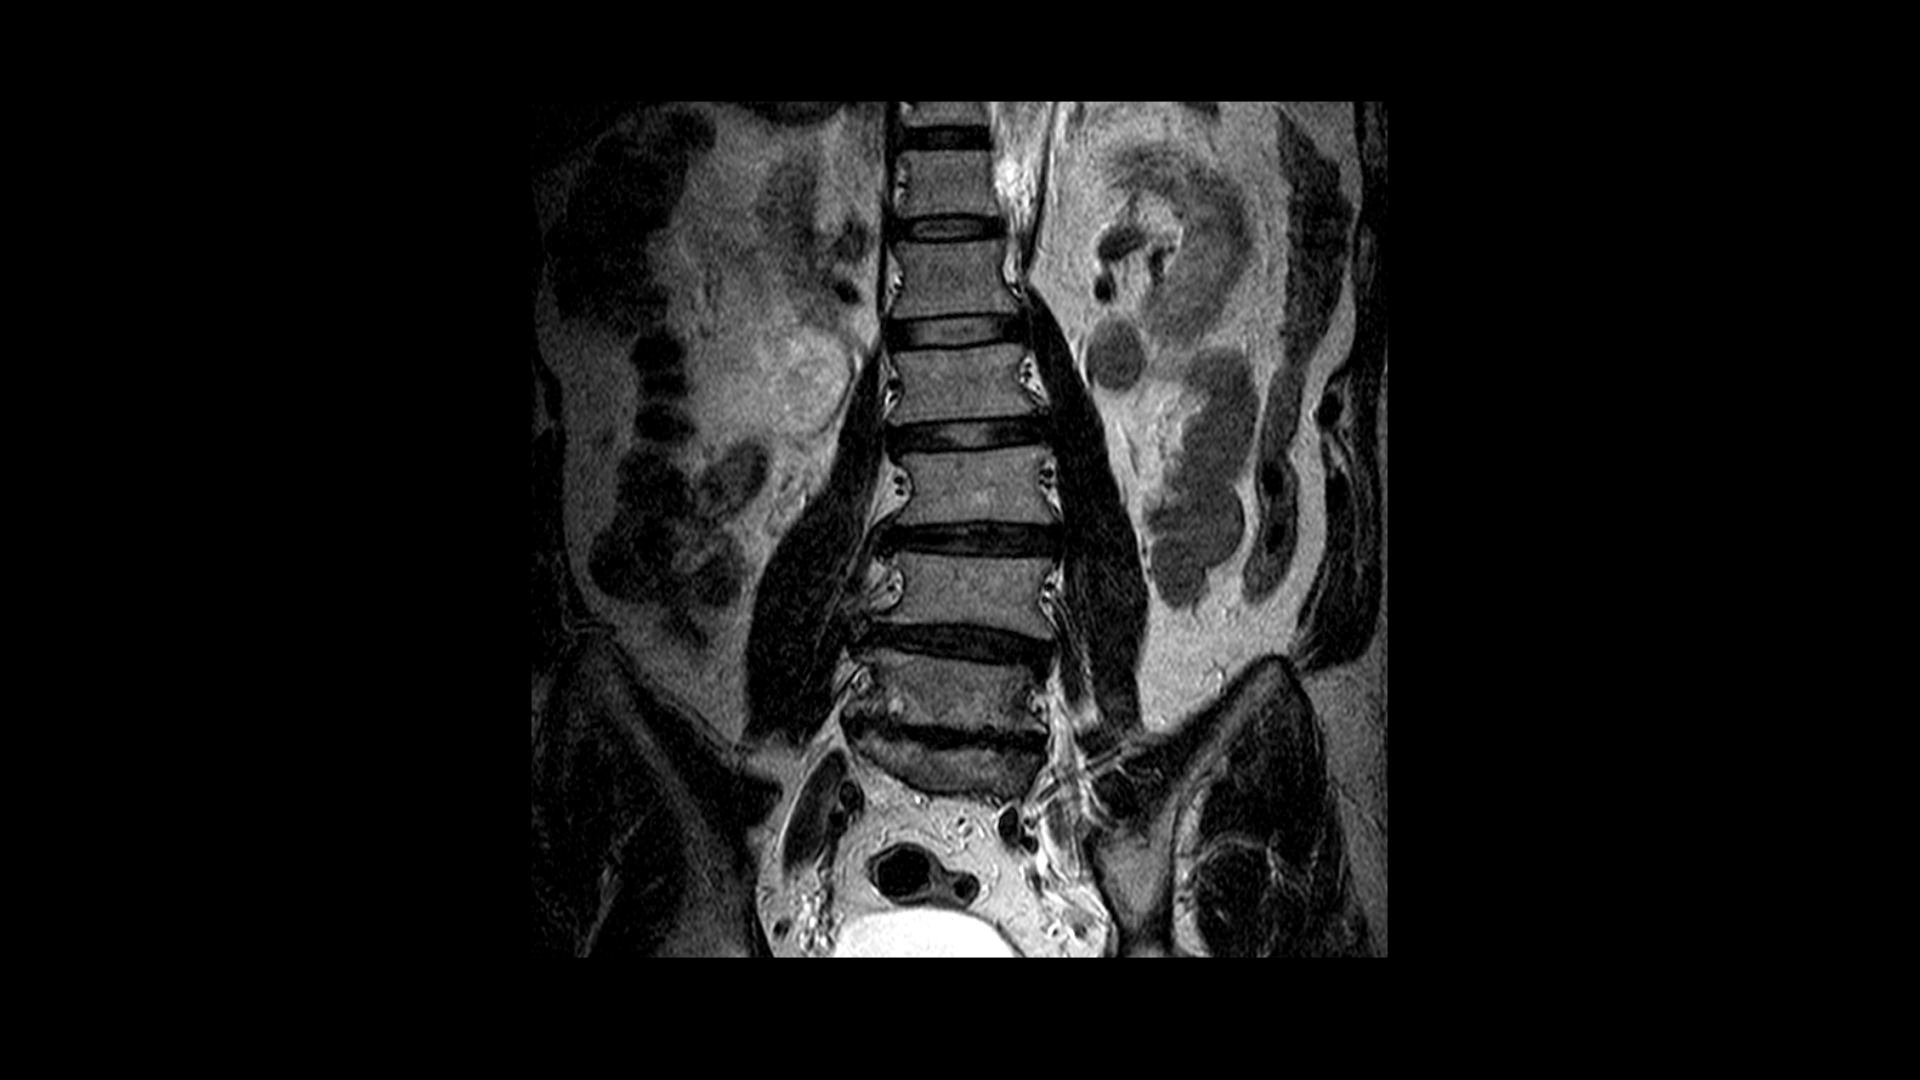

이분 척추를 정면에서 보면 보시다시피 많이 휘어있습니다.

이 환자만의 독특한 특징이 아니고 이렇게 오랫동안 허리가 아프신 60대 이후 환자분들의 허리를 보면 거의 대부분 예외없이 척추뼈가 다 휘어져 있습니다. 척추뼈가 휘어져 있다는 게 무슨 의미일까요?

척추뼈 주위의 근육이 불균형적으로 뭉치고 단축되고 굳어있고 아프다는 얘기입니다. 허리 주변근육들이 뭉치고 단축되고 굳어있으면 척추뼈들을 잡아당기기 때문에 척추뼈 사이사이로 빠져나가는 신경구멍을 더욱 좁게 만들어 신경을 더 눌리게 만드는 역할을 합니다. 이렇게 뭉치고 단축되고 굳어있는 근육 때문에 신경이 더 눌리게 되면 당연히 신경학적 증상, 즉 방사통도 심해지고 심지어는 마비 증상이 생길 가능성도 높아지는 겁니다.